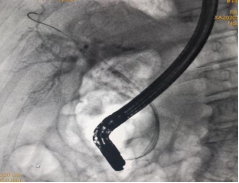

胆管插管成功,导丝进入胆管内……

(胆管插管成功,导丝进入胆管内) (胆管支架植入,解除胆道梗阻和胆道高压)

凭借扎实的ERCP专业功底和内镜操作技能,ERCP团队在短短20分钟就顺利完成了ERCP+EST+取石+ERBD+ENBD术,即胆总管造影、十二指肠乳头切开、胆总管末段嵌顿结石取出、胆总管支架植及鼻胆管引流术系列手术操作。

(ERCP术后胆管支架、鼻胆管X光线图片)